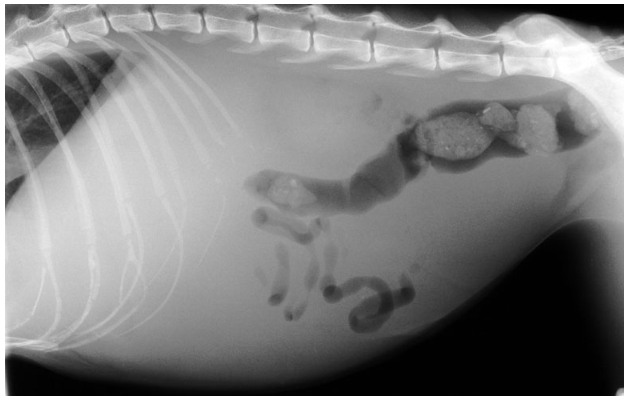

FIP Clinical signs 2 forms

Effusive (wet) form-more common

Non-effusive (dry) form